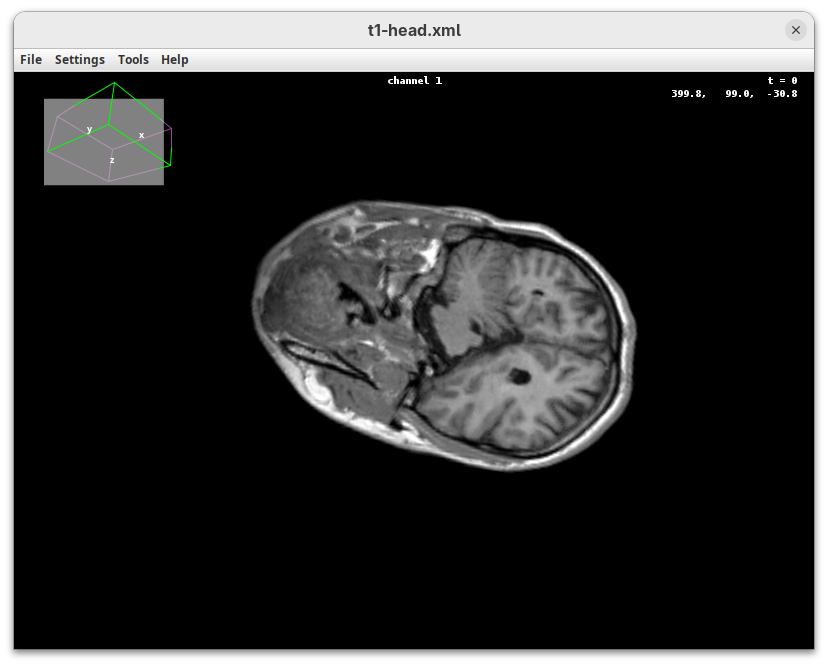

BigDataViewer (Pietzsch et al. 2015) is one of the most important tools for visualizing large, multidimensional datasets. It provides a simple and intuitive interface and shortcuts to swiftly navigate through your sample even on a regular laptop. This is possible because of the underlying file format used by BigDataViewer: the XML/HDF5 combo. Therefore, before opening the plugin, we must convert our dataset.

- Go to

Plugins>BigDataViewer>Export Current Image as XML/HDF5.

A dialog with export options will open.

- Under

Export path, click onBrowseto select the output directory fort1-head.xml.

The export process will start. Since this is a small dataset, it’ll be fast. But, for large datasets, this can take hours.

When done, you will find two new files in your working directory: t1-head.xml and t1-head.h5.

The XML file stores metadata information about the image. The HDF5 file stores actual image data. These two files will always be in a pair. To open the XML/HDF5:

- Go to

Plugins>BigDataViewer>Open XML/HDF5and select thet1-head.xml.

The BigDataViewer interface will open showing an optical section of the head sample.

Getting familiar with BigDataViewer is an essential skill for navigating large 3D datasets. It’ll also be important for the multiview registration pipeline. So, take the time to learn the basic commands and shortcuts. It is nicely intuitive. The BigDataViewer’s page on the ImageJ Docs has the official documentation and we can also go to Help > Show Help for an up-to-date overview.

Some of the movements to try:

Left-click and drag: turn the sample around the mouse pointer at any arbitrary angle.Right-click and drag: move the sample in the XY plane (of the view).Scroll: move through the Z plane (of the view). UseShift+Scrollto move fast.Ctrl+Shift+Scroll: zoom in or out.

But, most importantly, are the commands to put your sample back to its original orientation or along any of the original dimension axes:

Shift+Z: orient the sample on the XY plane.Shift+X: orient the sample on the ZY plane.Shift+Y: orient the sample on the ZX plane.

Finally, a visual tip. The default interpolation between image slices is nearest-neighbors. Press I to activate the tri-linear interpolation to obtain a much smoother (and improved) data visualization.